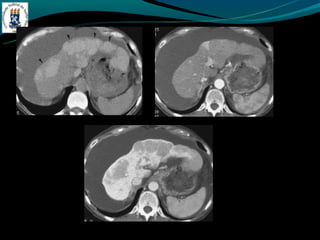

CIRROSE

NÓDULOS

- Nódulos regenerativos: 3-10mm, a maioria são isodensos, sinal

variável em T1, T2 hipo ou isointenso.

- Fibrose hepática confluente

- Áreas de fibrose semelhantes a massa, forma de cunha,

hipodensas, perda de volume da porção afetada do fígado

- São hiperintensas em T2 e hipo em T1.

CIRROSE NÓDULOS - Nódulos regenerativos: 3-10mm, a maioria são isodensos, sinal variável em T1, T2 hipo ou isointenso.

CIRROSE - Fibrose hepáticaconfluente - Áreas de fibrose semelhantes a massa, forma de cunha, hipodensas, perda de volume da porção afetada do fígado - São hiperintensas em T2 e hipo em T1.